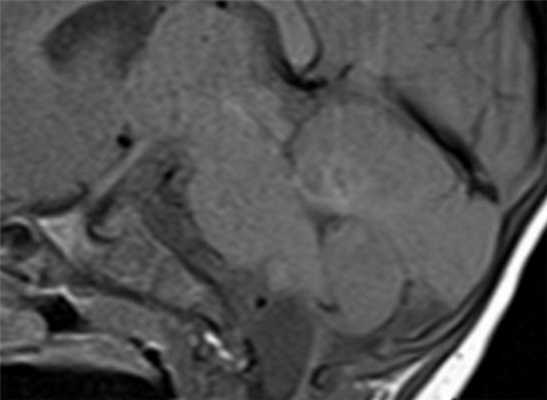

![эхинококк головного]()

МРТ головного мозга. Корональная Т1-взвешенная МРТ. Многокамерные эхинококковые кисты.